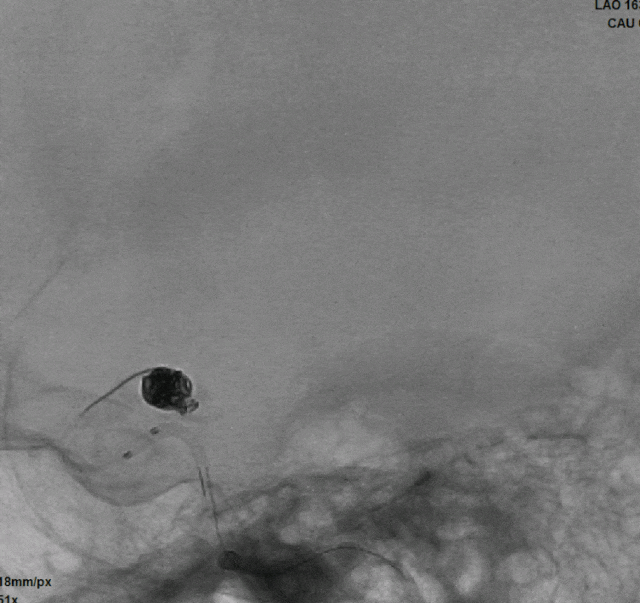

术后即刻影像

本例病例为带有子囊的后交通动脉瘤伴胚胎型大脑后动脉,为了降低术中破裂风险,提高安全性和栓塞效果,采用双微导管技术,同时弹簧圈的均匀分布,柔顺性和钻缝能力同样重要,Jasper®SS弹簧圈展现出了非常优秀的柔顺性和较强的钻空能力,在整个填塞过程中没有出现踢管现象,增加了动脉瘤栓塞的致密性,降低了术者操作的难度。